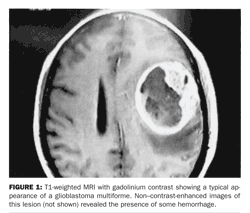

MRI The diagnosis of a brain tumor is best made by cranial MRI. This should be the first test obtained in a patient with signs or symptoms suggestive of an intracranial mass. MRI is superior to

CT and should always be obtained with and without contrast material such as gadolinium.

High-grade or malignant primary brain tumors appear as contrast-enhancing mass lesions that arise in white matter and are surrounded by edema (Figure 1). Multifocal malignant gliomas are seen in ~5% of patients.